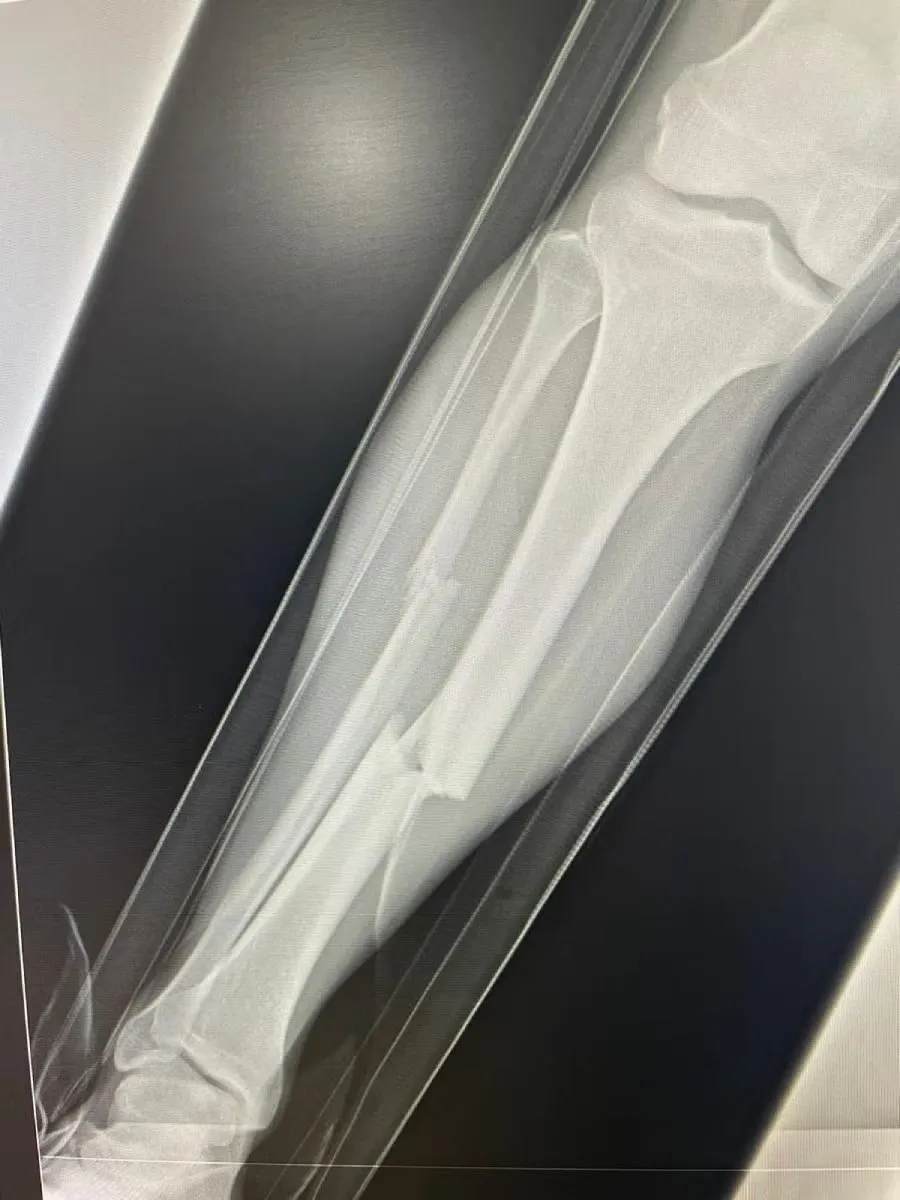

Las imágenes del momento, tanto en video como en fotografías, mostraron claramente la gravedad del impacto, lo que provocó un conato de bronca entre jugadores de ambos equipos. El mediocampista fue trasladado inmediatamente al hospital, donde se le diagnosticó una fractura de tibia y peroné.

El propio club Atlante confirmó el diagnóstico días después del partido. La lesión de fractura doble obligó a Bermúdez a pasar por un proceso de recuperación prolongado, que podría extenderse hasta seis u ocho meses, dependiendo de la complejidad del caso y la necesidad de intervención quirúrgica.

En las imágenes compartidas por el club, se observó un ligero desplazamiento óseo, lo que reforzó la necesidad de una posible cirugía para estabilizar la zona afectada.